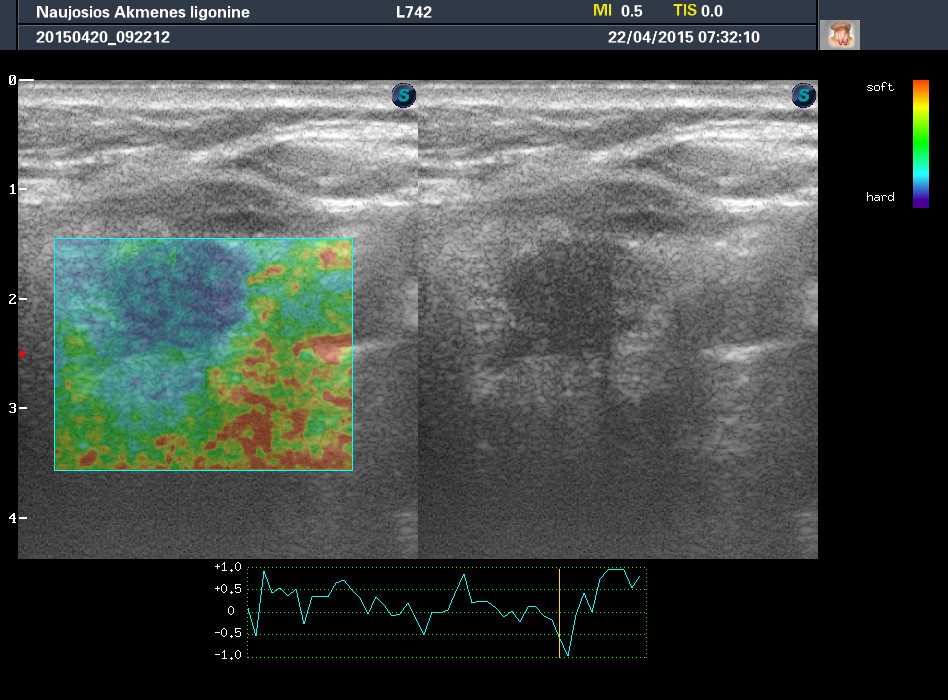

Случай 1

Женщина 67 лет, жалоб нет. Рост узла за год +3 мм. Регионарные ЛУ не увеличены.

1-й узел злокачественный, а 2-й ,скорее всего, доброкачественный. Но,понятное дело, нужна пункция и было бы здорово узнать результат.

Согласна с Anastasia.:-) И,простите, что за исследование на сканах, не на видео? Я такого не делаю и,к сожалению, не знаю,как интерпретировать его(

Mattiola писал(а): И,простите, что за исследование на сканах, не на видео? Я такого не делаю и,к сожалению, не знаю,как интерпретировать его(

Эластография. http://www.medison.ru/si/art380.htm

Цитология 1 случая - злокачественных клеток не обнаружено.